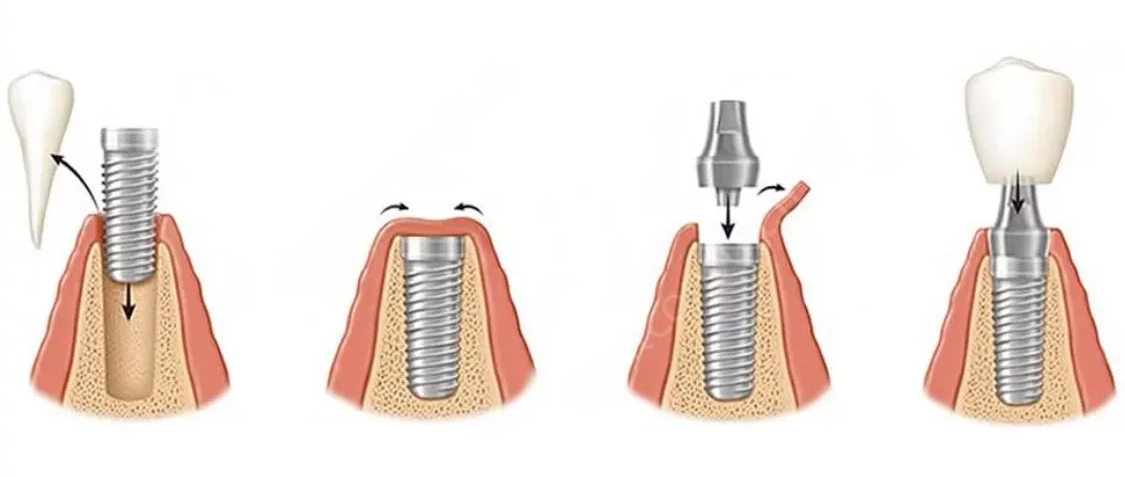

Двухэтапная

Данный метод считается наиболее эффективным. На первом этапе устанавливается только внутрикостный имплантат, а на втором этапе происходит протезирование. Между первым и вторыми этапами должно пройти минимум 3-4 месяца.

1 этап-хирургический:

- рассечение десны (готовится ложа для имплантата);

- устанавливается имплантат;

- ушиваются десневые ткани для изоляции имплантата.

Через 3 месяца после после полного приживления имплантата ткани десны повторно рассекают и устанавливают формирователь десны (готовится место для коронки).

2 этап-ортодонтический: через 3 недели после установки формирователя десны начинается протезирование.